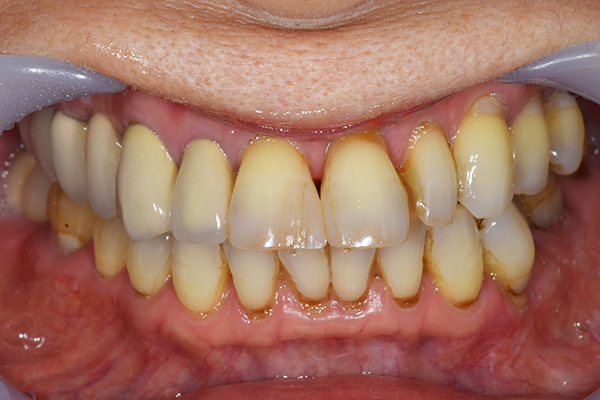

前歯が折れて当院にいらっしゃいました。 過去に下の入れ歯を作ったが、合わなくなってずっと入れ歯をいれていらっしゃらない患者様でした。 これは奥歯で噛むことができないため、前歯で噛むことを繰り返したために、負担に耐えられなくなった前歯が折れてかぶせ物ごと 外れてしまったのだと考えられます。 痛くない、違和感の少ない、下の入れ歯を作ることがこの方のゴールであると考えられました。

入れ歯をお口の中にいれた状態です。前歯もMTMといって、歯を少し引っ張り出す処置を行なったことで、しっかり残せて、またかぶせ物をしました。

年齢 70歳・女性

主訴 前歯が取れた

治療期間 8ヶ月

治療費 .MTM:110,000円

.ファイバーコア:16,500円

.E-maxクラウン:110,000円

.義歯:660,000円

治療方針 長年使ってきた義歯の人工歯が磨耗し、臼歯部での咬合がすくなくなり、前歯部での接触が強くなったことで生じた前歯の破折なので、義歯も作り変える必要がある。

治療内容 前歯部MTMと同時に審美面の回復。

MTM中に義歯の作成も同時に行う。

最終的に義歯と前歯のクラウンを同時にいれる。

義歯は下顎で、しっかり噛めること、違和感の少ないものという希望があったため、なるべく入れ歯を薄く作成するために金属をしようした義歯とした。

また、見た目もあまり義歯が目立たない様に、バネの部分を見えにくいように作成した。

特記事項 歯にもともと入っていた金属の種類によっては、歯自体の変色を治療で変えられないこともある。 義歯は作ってから痛みがでることがありますが、それは調整を行うことで痛くなくすることができます。